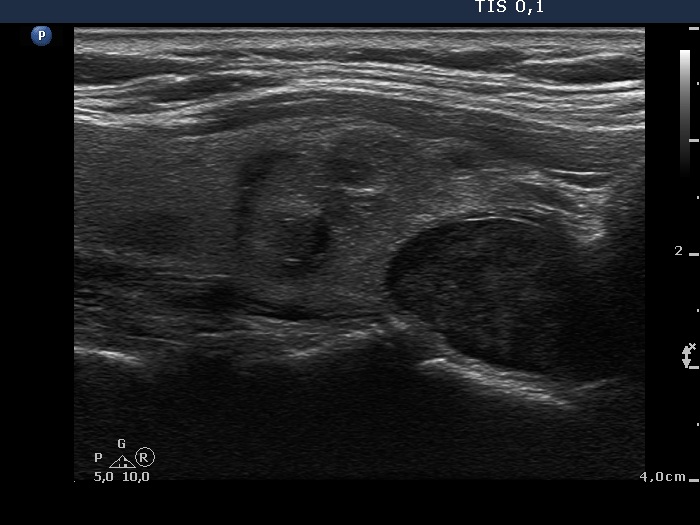

Ultrasonography: The thyroid was echonormal and contained multiple inhomogeneous, hyperechogenic nodules. There was a hypoechogenic lesion in the dorsal part or dorsal to the lower pole of the right lobe.

Total thyroidectomy was performed with the removal of the right lower parathyroid. Histopathology: benign, hyperplastic nodules in both lobes and a parathyroid adenoma corresponding to the right lower parathyroid.